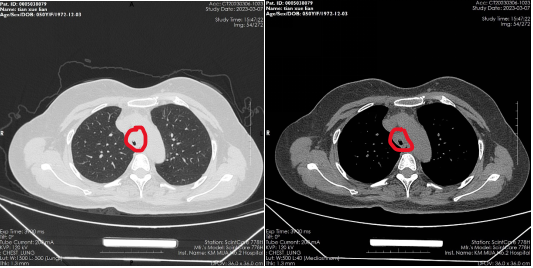

患者,女,50岁,因“外伤后呼吸困难2月”来到财神捕鱼玩法攻略与赚钱技巧指南 | 财神捕鱼游戏网 全科医学科治疗。患者2月前因外伤致气管撕裂,在当地财神捕鱼 行气管修补术,术后出现进行性加重呼吸困难。患者来到我院住院后,稍微活动就会感到气促,已不能活动,肺功能显示重度阻塞性肺通气功能障碍,胸部CT显示气管下段重度狭窄,支气管镜检查显示气管下段距隆突2cm处重度瘢痕狭窄,最窄处仅4mm,随时都会发生窒息甚至猝死,手术迫在眉睫!

气管下段狭窄治疗前